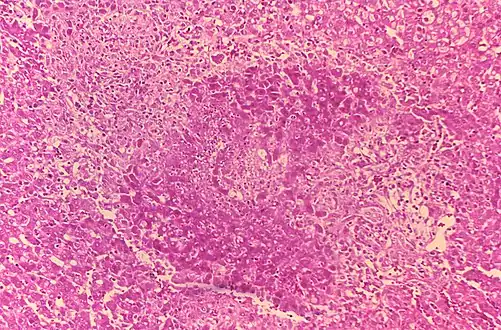

Processed using the Gram-stain method, photomicrograph revealed the presence of numerous Gram-negative, coccobacillus, Brucella suis bacteria.

- Histologic evidence of granulomatous hepatitis on hepatic biopsy